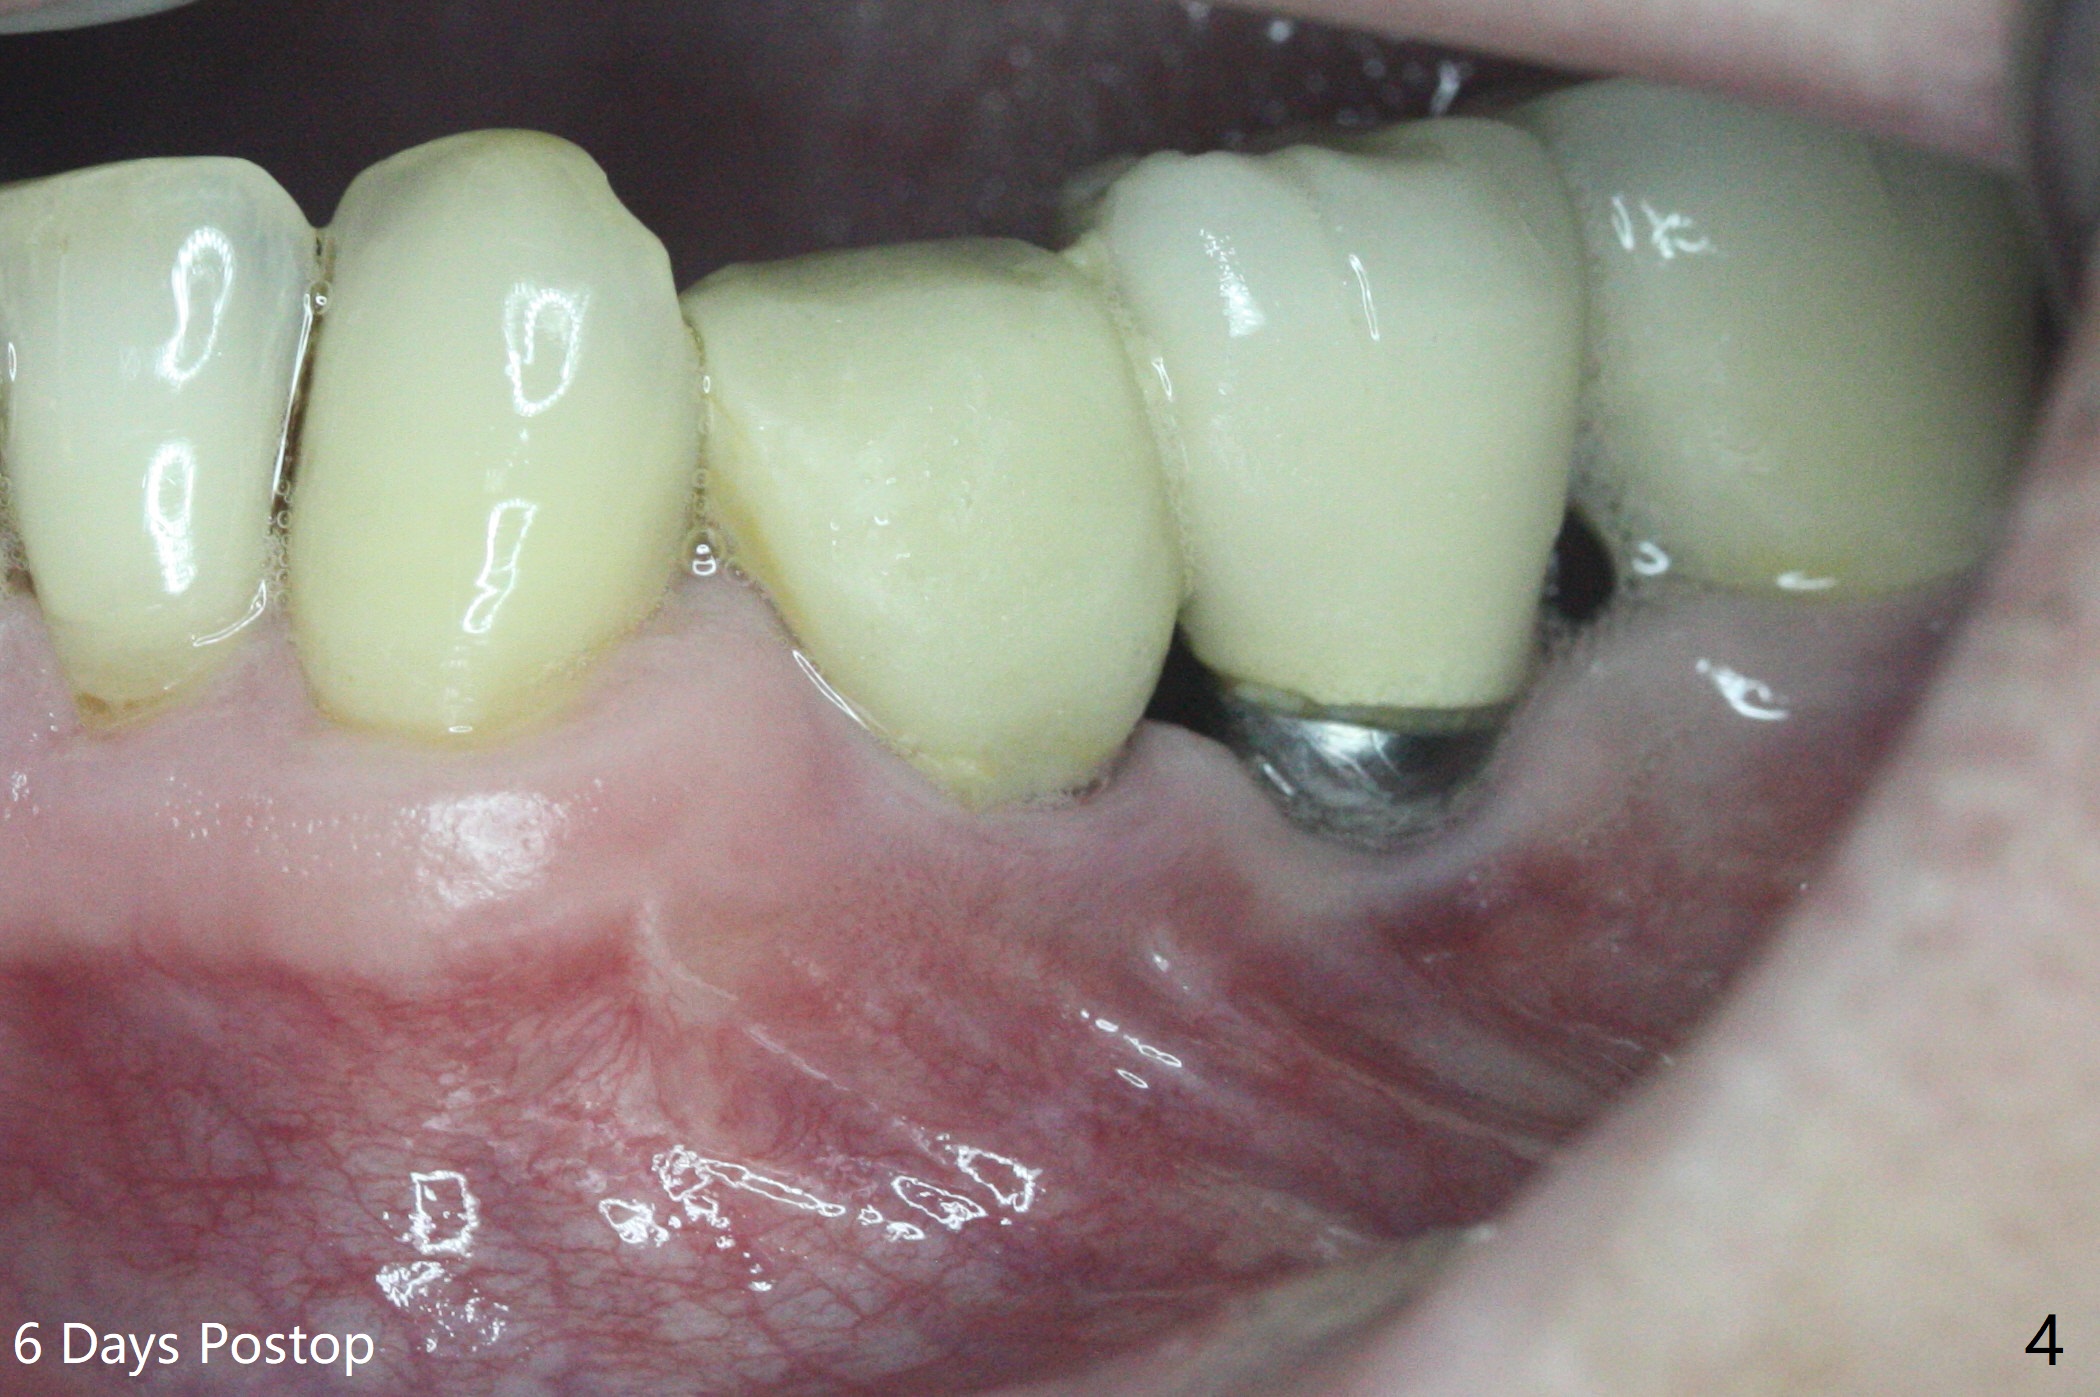

尽管使用导板,钻洞也不快,左下4植体仍旧偏移远中(图一)和颊侧(颊侧间隙比预计小),原因:斜面(图一:箭头),骨质硬,周围牙冠射线折射,导板就位前必须磨第二前磨牙近中面(今后遇到这些情景,选择徒手种植)。庆幸的是牙槽嵴水平两个植体还不是最接近(与根尖相比),粘性植骨(图一:*)但愿能缓解术后骨质吸收。制作临时牙冠后(图二:P),将PRF(图二:^;三:L(舌侧))插入牙冠和骨粉之间。术后六天软组织愈合正常(图四)。术后4个月远中牙槽嵴稍微下降(图五:*)。由于基台偏向远中,为了防止牙冠基台重新插入困难,基台不取出,先拧紧(20Ncm),牙冠口内粘固。